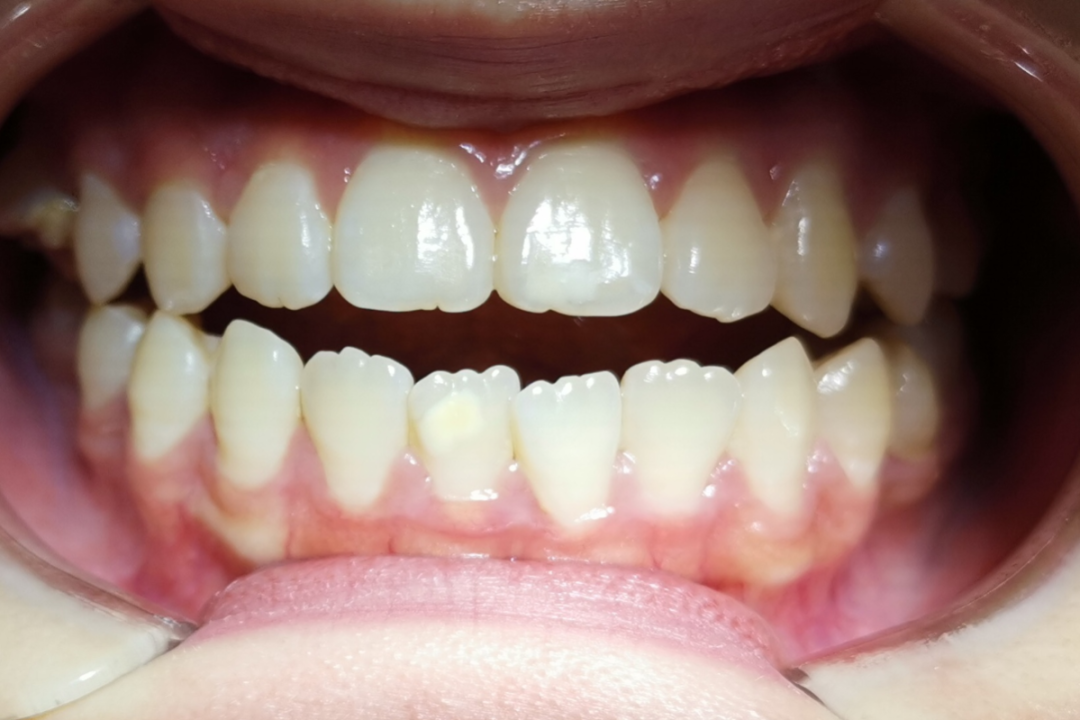

金属自锁托槽矫治技术

治疗前                        治疗后

无托槽隐形矫治技术